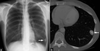

Nódulo pulmonar solitário:

uma única opacidade pulmonar arredondada, bem circunscrita, envolta por parênquima pulmonar normal, com diâmetro menor ou igual a 3 cm e não associada à linfoadenomegalia mediastinal, pneumonia, atelectasia ou derrame pleural

Lesões pulmonares com diâmetro maior que 3 cm:

Massas pulmonares